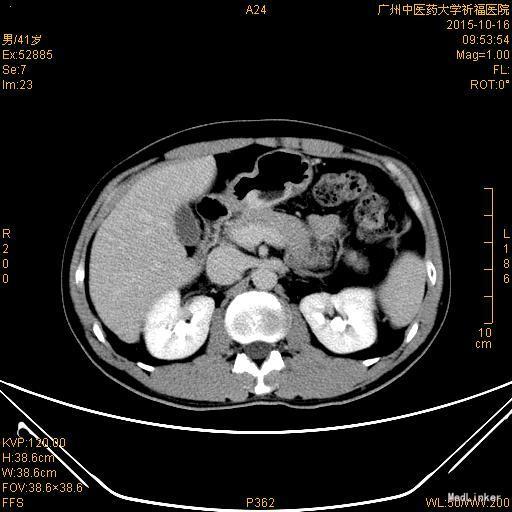

诊断:胃癌(胃窦中分化腺癌) 入院后完善相关术前检查无明显异常,排除手术禁忌症,经科室讨论治疗方案,于2015-10-23送手术室在气管插管全麻下行“腹腔镜远端胃癌根治术”。术程顺利,术后予以心电监护,低流量吸氧,制酸、护胃、抗感染、肠外营养等治疗。术后病理报告:胃中分化腺癌,蕈伞型,大小分别为3.0cmx1.5cmx1.5cm,2.0cmx1.0cmx1.0cm,浸润胃壁全层,可见坏死、脉管及神经侵犯。近端、远端两切缘未见癌累及。淋巴结见转移癌(第一组0/0,第八组0/2,第十一组0/0,胃小弯侧12/14,胃大弯侧8/9,大网膜0/0,结内癌巢最大直径1.5cm)。免疫组化结果显示:CK20(-),CK7(+),GST-π(++),HER2(-),Ki-67(50%+),P53(80%+),PgP(+),TOPOII(+),villin(+)。10-29 复查血常规:WBC 7.47×10^9/L,RBC 4.25×10^12/L,PLT 220×10^9/L,HGB 123g/L,Neu% 75.0%,CRP 20.2mg/L;肝肾功、电解质无明显异常。患者外科情况稳定后转肿瘤内科进一步治疗。